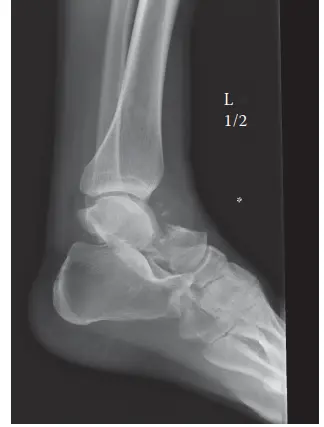

الأشعة السينية X-ray

تُعد الأشعة السينية هي الخطوة التشخيصية الأولى والأكثر أهمية في قسم الطوارئ. تُؤخذ عدة لقطات (أمامية خلفية، جانبية، ومائلة) للكاحل والقدم المصابة. في حالة كسر عنق الكاحل من النوع الثالث، تُظهر الأشعة السينية بوضوح:

*

كسر عنق الكاحل:

يكون الكسر واضحًا في منطقة عنق عظم الكاحل، وغالبًا ما يكون مصحوبًا بانزياح شديد.

خلع جسم الكاحل:

يظهر جسم عظم الكاحل (الجزء الخلفي) منخلعًا من مفصل الكاحل، وغالبًا ما يكون متراجعًا إلى الخلف خلف عظم الظنبوب.

خلع مفصل تحت الكاحل:

يظهر خلع في مفصل تحت الكاحل، حيث يبقى جزء العنق والرأس المكسور من عظم الكاحل متصلاً بعظم العقب، ولكنه يكون منحرفًا عن مكانه الطبيعي.

توسع في مفصل الكاحل:

قد يشير إلى إصابة في الأربطة المحيطة.

بناءً على الأشعة السينية، يتم تصنيف الكسر وفقًا لتصنيف هوكينز (Hawkins Classification)، وهو نظام أساسي لتقدير خطر النخر اللاوعائي (AVN):

صورة شعاعية توضيحية لكسر معقد في عظم الكاحل، تُظهر نمط الكسر الأولي ومحاولات التثبيت.